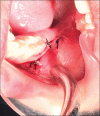

Aim: The present study aimed to comparatively evaluate the clinical outcomes and periodontal status of the adjacent second molar, when two different flap designs, namely, the envelope and the modified triangular flap designs were used.

Materials and methods: Sixty female patients with bilateral impacted third molars completed the study with envelope flap on one side and modified triangular flap design on the other side of the mandible for third molar removal. Clinical parameters including pain, dehiscence and swelling were assessed postoperatively and periodontal probing depth (PPD) on the distal aspect of adjacent second molar were assessed both pre- and post-operatively.

Conclusion: The study revealed that the modified triangular flap had lesser postoperative PPDs and dehiscence. The envelope flap was better when swelling was analyzed. The pain scores, though slightly higher for the modified triangular flap group, were not statistically significant.